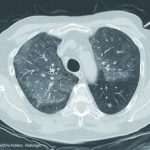

Somit ist im Verlauf der Krankheit die Spannbreite der klinischen Darstellungen groß. Bei therapieresistenten Infiltraten, insbesondere der Lungenoberlappen, ist an die Tuberkulose zu denken. Die Abb. 4 zeigt eine Tuberkulose bei guter immunologischer Abwehrlage des Patienten und ließe beispielsweise auch an eine Raumforderung denken. Daneben sind alle Bilder von „normalen“ Pneumonien denkbar. Der chronische Verlauf mit Ausbildung von Veränderungen, die sich durch den andauernden Entzündungsprozess entwickeln wie Lungengerüstumbau, narbige Verziehungen und Entstehen von Kavernen lassen oft mehr oder weniger sicher eine Tuberkulose bereits radiologisch erkennen. Der Patient aus der Fallvignette zeigte CT-radiologisch das in Abb. 5 gezeigte Bild einer Miliartuberkulose, das schon fast an eine Lungengerüstkrankheit erinnert. Zusätzlich bestand bei diesem Patienten das Bild einer Abdominaltuberkulose mit Aszites.